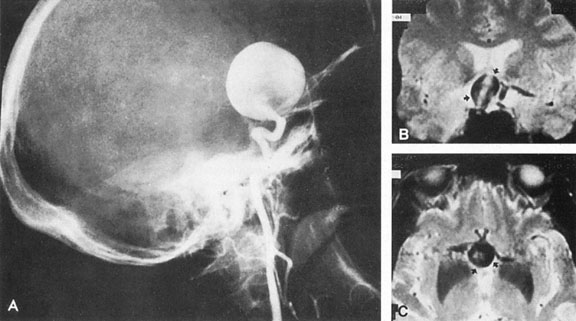

Vertebrobasilar System

Tortuous or redundant basilar arteries are not uncommon in the older age group. Occasionally, gross dilation or ectasia develops so that the basilar artery acts as a mass in the posterior fossa. This phenomenon produces signs of low-pressure hydrocephalus, cranial nerve palsies, and long tract and sensory signs and may even simulate a cerebellopontine angle tumor or tumor at the foramen magnum.58 It is possible to diagnose such lesions with CT59 or MRI60 but angiography is definitive (Fig. 6). The association of insidious multiple cranial nerve palsies and long tract signs referable to a brainstem level, in an elderly patient with evidence of atherosclerosis, should make fusiform basilar artery dilation a diagnostic consideration.

Fig. 6. Fusiform basilar dilation. A: Lateral projection vertebral arteriogram showing a widened basilar artery (arrow) projecting beyond level of dorsum sellae. B: Anteroposterior projection showing a widened and tortuous basilar artery.